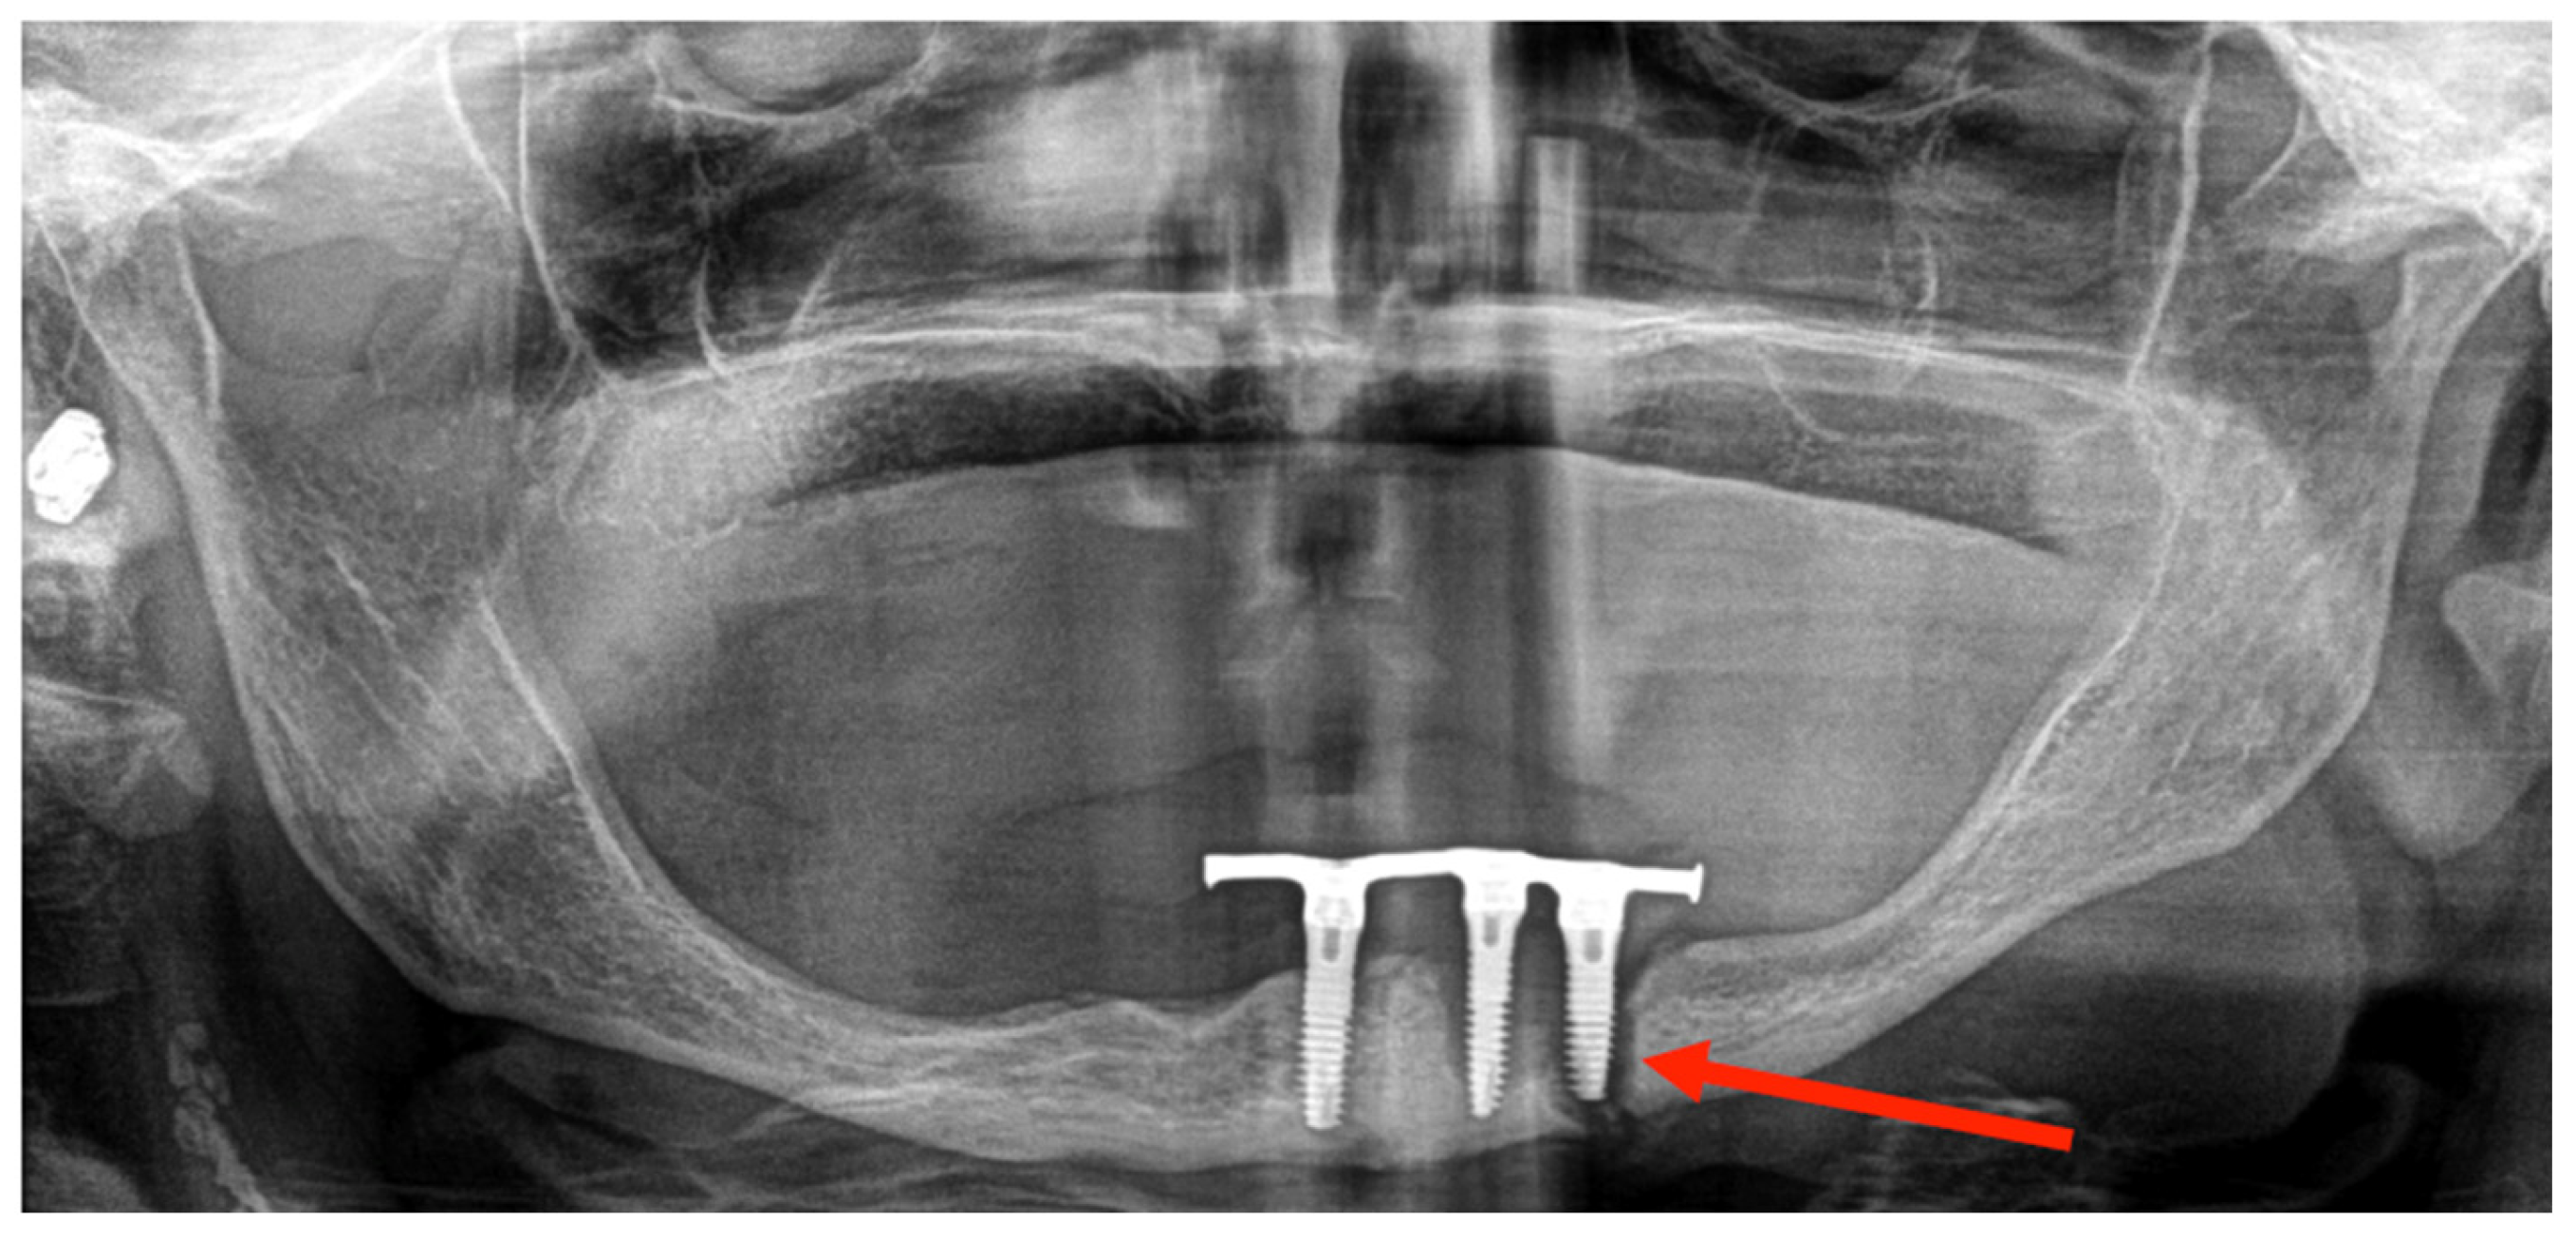

3.1. Case 1

3.2. Case 2

| Diagnostic imaging studies | Orthopantomography (OPG) | 6 (100%) |

| Location | Left parasymphyseal | 2 (33.3%) |

| Left body | 3 (50%) | |

| Bifocal (left body and right ramus) | 1 (16.67%) | |

| Fracture pattern | Simple | 5 (83.3%) |

| Bifocal | 1 (16.67%) | |

| Etiology | Peri-implantitis | 3 (50%) |

| Traumatism | 1 (16.67%) | |

| Osteonecrosis | 2 (33.3%) | |